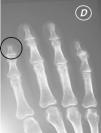

La radiografía de manos demostró la reabsorción ósea de la falange distal del dedo índice de la mano derecha (fig. 3).